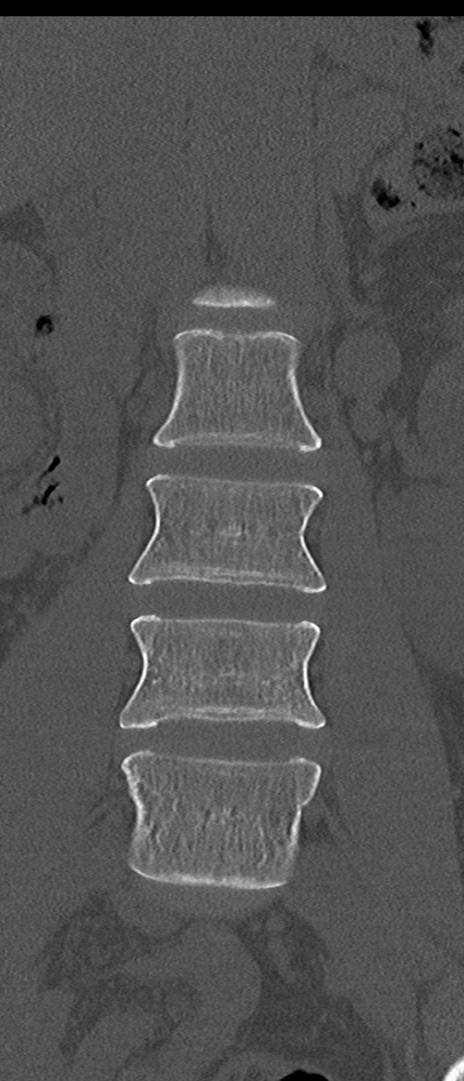

【整形】TIPS症例4 腰椎CT(冠状断像)

腰椎CT